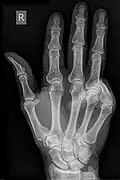

Acquired hand deformity refers to the structural or functional abnormalities that develop in the hand. There are multiple varying causes of acquired hand deformity, triggering significant consequences and complications. Trauma, including blunt force, penetrating injuries, burns, and sports-related incidents, is a primary cause of acquired hand deformities. Inflammatory conditions such as rheumatoid arthritis, gouty arthritis, and systemic lupus erythematosus can also contribute to hand deformities by affecting the joints. Degenerative arthritis, specifically osteoarthritis, functions to evoke impaired hand function due to the gradual deterioration of cartilage. Neurological disorders like cerebral palsy can result in hand contractures due to increased muscle tone and stiffness. There are different types of acquired hand deformities, each with distinct characteristics and underlying causes, such as boutonnière deformity, Dupuytren's contracture, gamekeeper's thumb, hand osteoarthritis deformity, mallet finger, swan-neck deformity, ulnar claw hand, among many others.

The consequences and complications of acquired hand deformities vary based on the nature of their causes. Acute-event deformities can limit finger movement and produce possible grip implications, while chronic-event deformities may also progressively impair joint function. Abnormal joint growth, burn-specific trauma, and hand amputation evoke functional limitations. Diagnostic pathways are imperative to assess the status and extent of deformities, evaluate nerve function, and visualise damage. These pathways can involve nerve testing, physical examinations, lab tests, and imaging examinations.